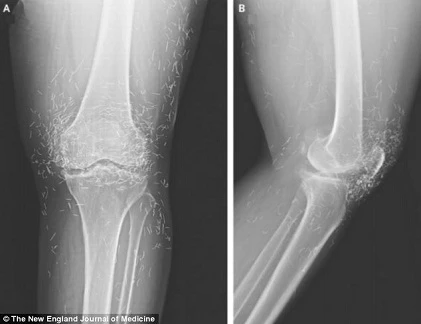

(Kiến Thức) - Các bác sĩ đã bị sốc khi họ chụp X-quang đầu gối của một phụ nữ và thấy rất nhiều kim vàng.

Người phụ nữ Hàn Quốc, 65 tuổi, đã có hàng trăm kim châm cứu nhỏ trong mô đầu gối. Người ta cho rằng chúng được cố ý bỏ lại bởi chuyên gia châm cứu đang điều trị viêm xương khớp cho bà.

Điều trị bằng châm cứu có tác dụng kích thích các bộ phận khác nhau của cơ thể hoặc để giảm đau. Trong trường hợp này, người ta cho rằng kim còn sót lại bên trong đầu gối của cô là cố ý để tiếp tục kích thích sau khi điều trị đã kết thúc.